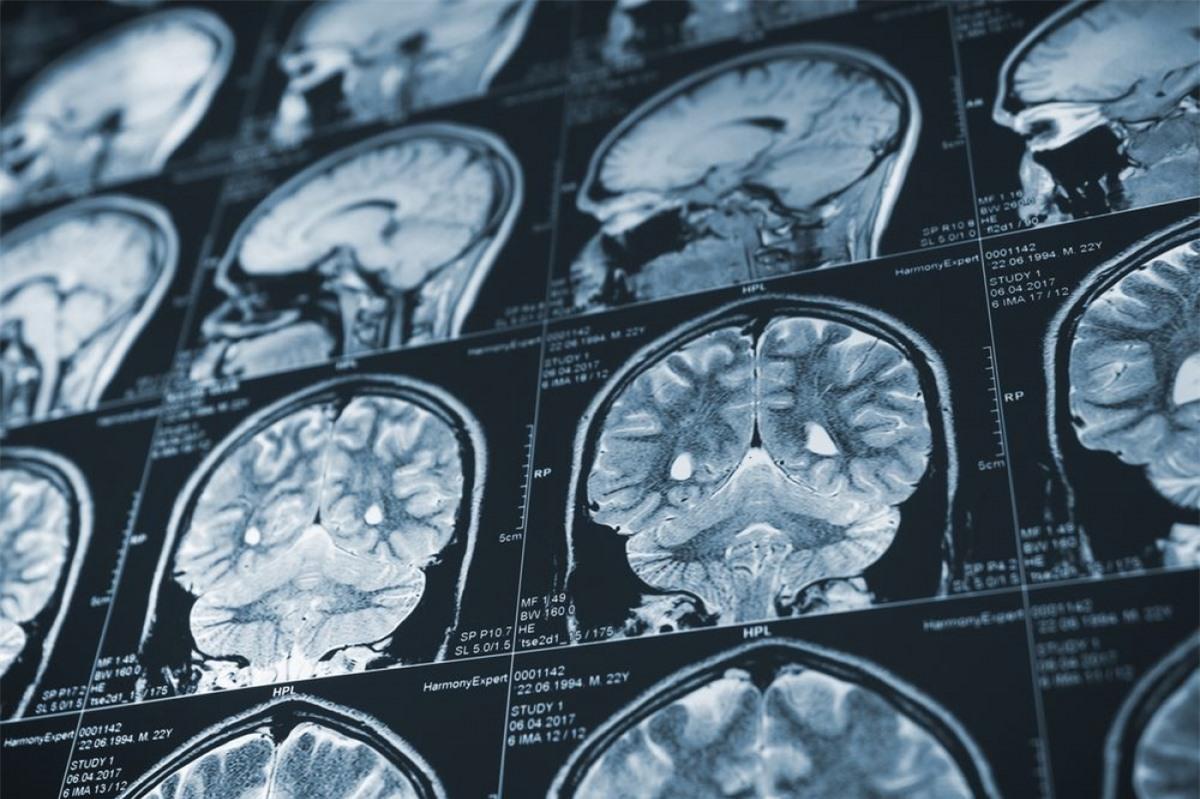

Đột quỵ: Đột quỵ là tình trạng xảy ra khi lưu thông máu bị gián đoạn, thường là do đông máu hoặc chảy máu ở não bộ. Những cơn đột quỵ ở hành não, ảnh hưởng đến khả năng hô hấp có thể gây tử vong tại chỗ. Người sống sót sau cơn đột quỵ cũng có thể bị liệt một phần cơ thể, gặp khó khăn trong việc nói chuyện và các khuyết tật khác.

Bệnh Alzheimer và các chứng suy giảm trí nhớ khác: Mặc dù không trực tiếp gây tử vong, nhưng bệnh Alzheimer cũng là một trong những nhân tố làm giảm tuổi thọ hoặc gây các biến chứng nguy hiểm. Khi bệnh trở nặng, người bệnh sẽ gặp khó khăn trong việc kiểm soát các vận động như đi lại hay nuốt thức ăn.